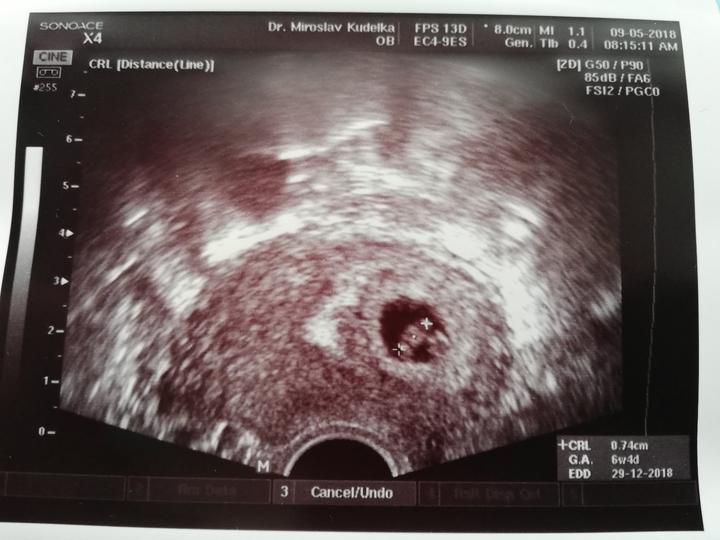

Už ať je středa 9.5., naše první kontrola u pana gynekologa, snad bude vše vporadku a uvidíme tlouct 💓 😊 a odneseme první fotečku🤰

9.5. Budeme mít první ultrazvuk 7 tt😍